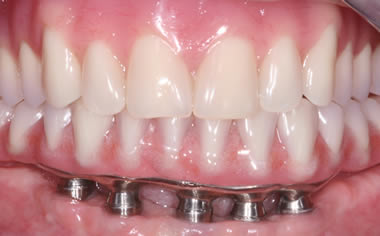

Full arches of teeth replaced by dental implants

Case One (5 images)

Full set of lower teeth fixed onto five dental implants.